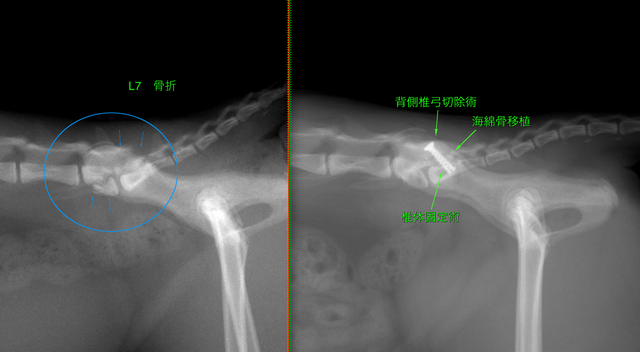

腰仙椎固定術(不安定症・脱臼・骨折)

L7 骨折